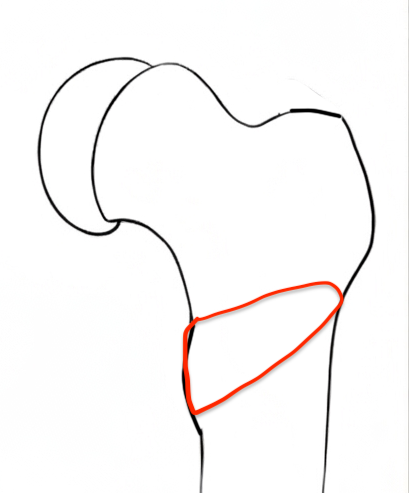

Intertrochanteric / Southwick

Technique

Removal anterolateral bone wedge below lesser trochanter

Valgising / flexion / internal rotation